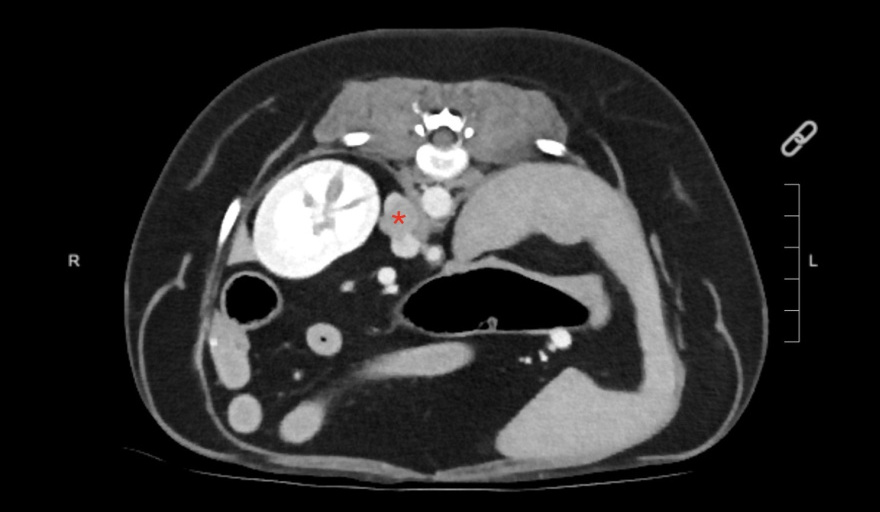

El feocromocitoma es un tumor de la médula suprarrenal que afecta tanto a perros como a humanos. Produce un exceso de hormonas como la epinefrina y la norepinefrina y puede causar complicaciones cardíacas potencialmente mortales.

En la medicina veterinaria, este tumor poco frecuente pero de gran relevancia clínica, suele pasar desapercibido debido a signos clínicos inespecíficos -como hipertensión, colapsos o taquiarritmias- que se confunden con otras afecciones hormonales o cardiovasculares.